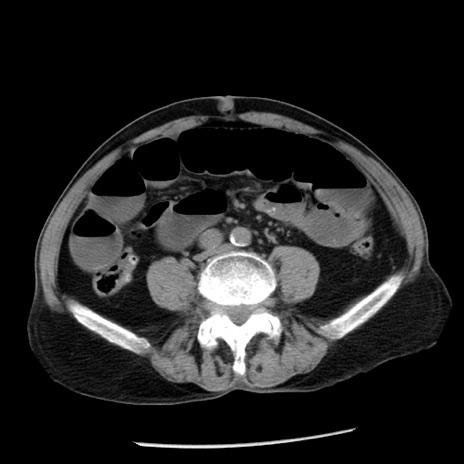

症例26(横断像)

【症例】80歳代男性

【主訴】嘔吐

【現病歴】昨晩2回嘔吐あり、今朝になっても嘔吐あり。来院。

【既往歴】胃潰瘍

【身体所見】意識清明、BT 37.6℃、BP 166/95mmHg、HR 100bpm、SpO2 97%、腹部:平坦・軟、腸蠕動音聴取良好、圧痛なし。

【データ】WBC 21900、CRP 1.46